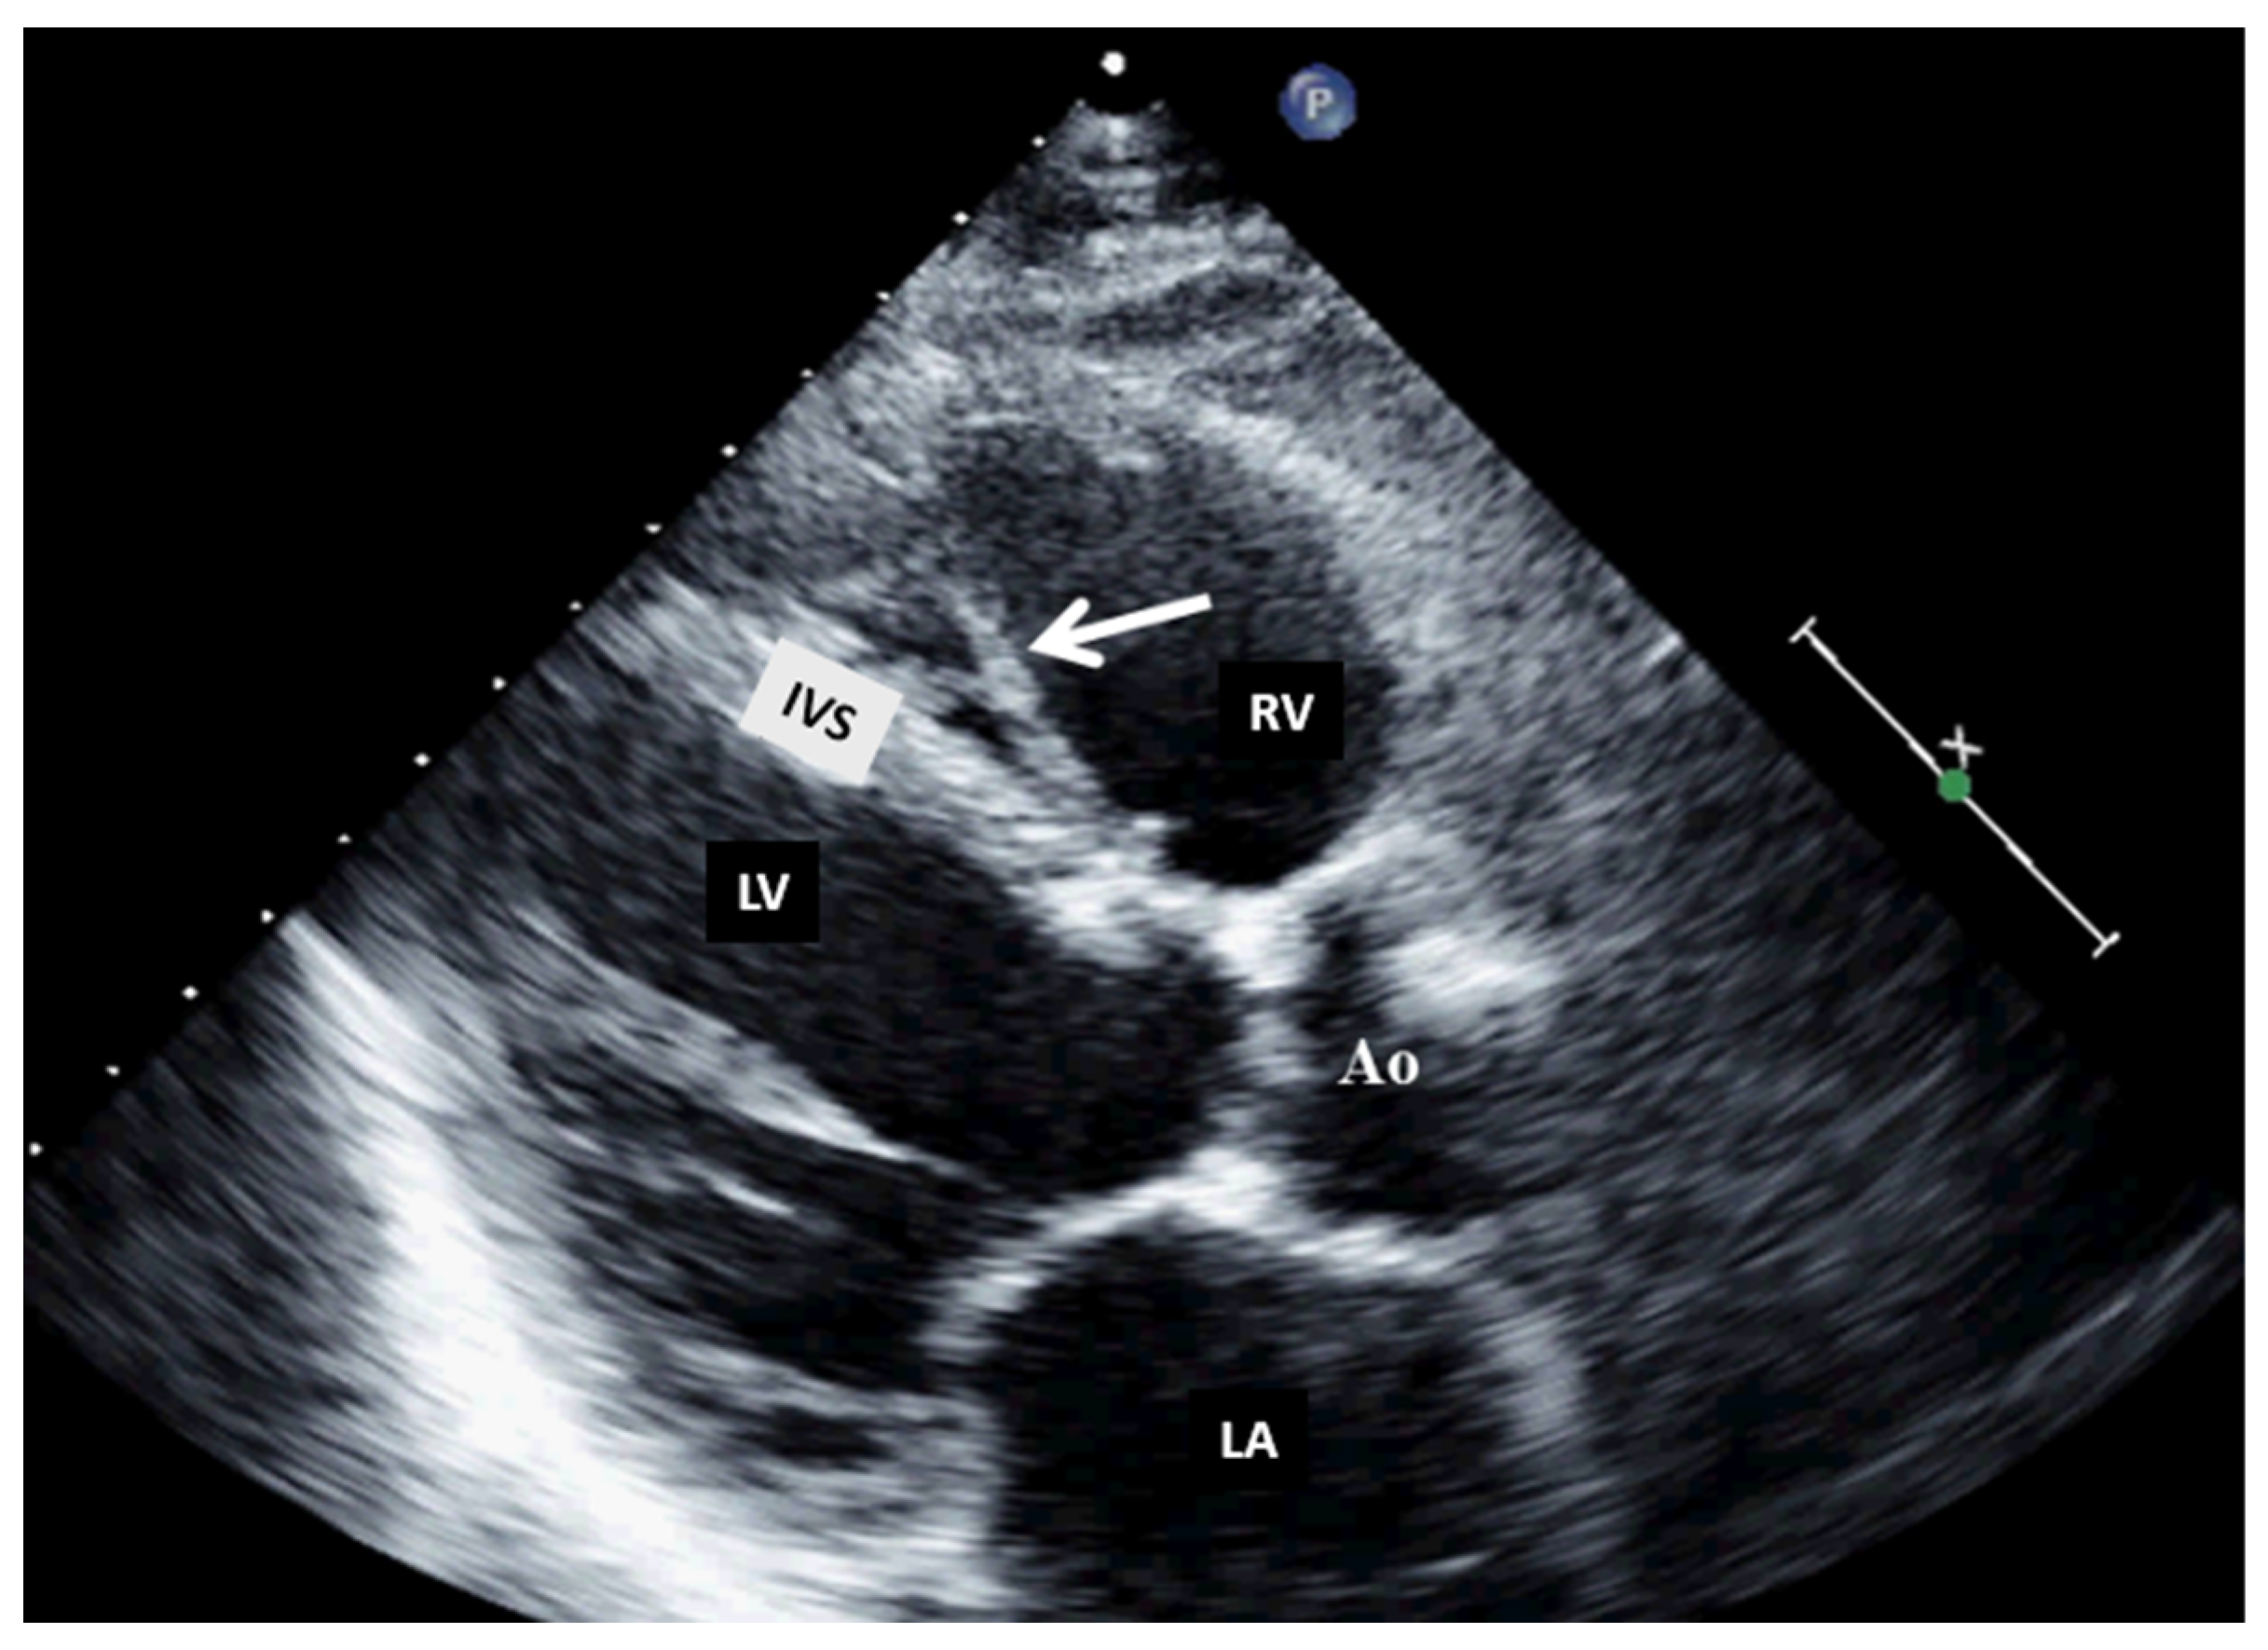

Figure 4.

Two-dimensional transthoracic echocardiography (modified parasternal view, long axis) showing a moderator band in the right ventricle. Ao, aorta; IVS, interventricular septum; LA, left atrium; LV, left ventricle; RV, right ventricle.